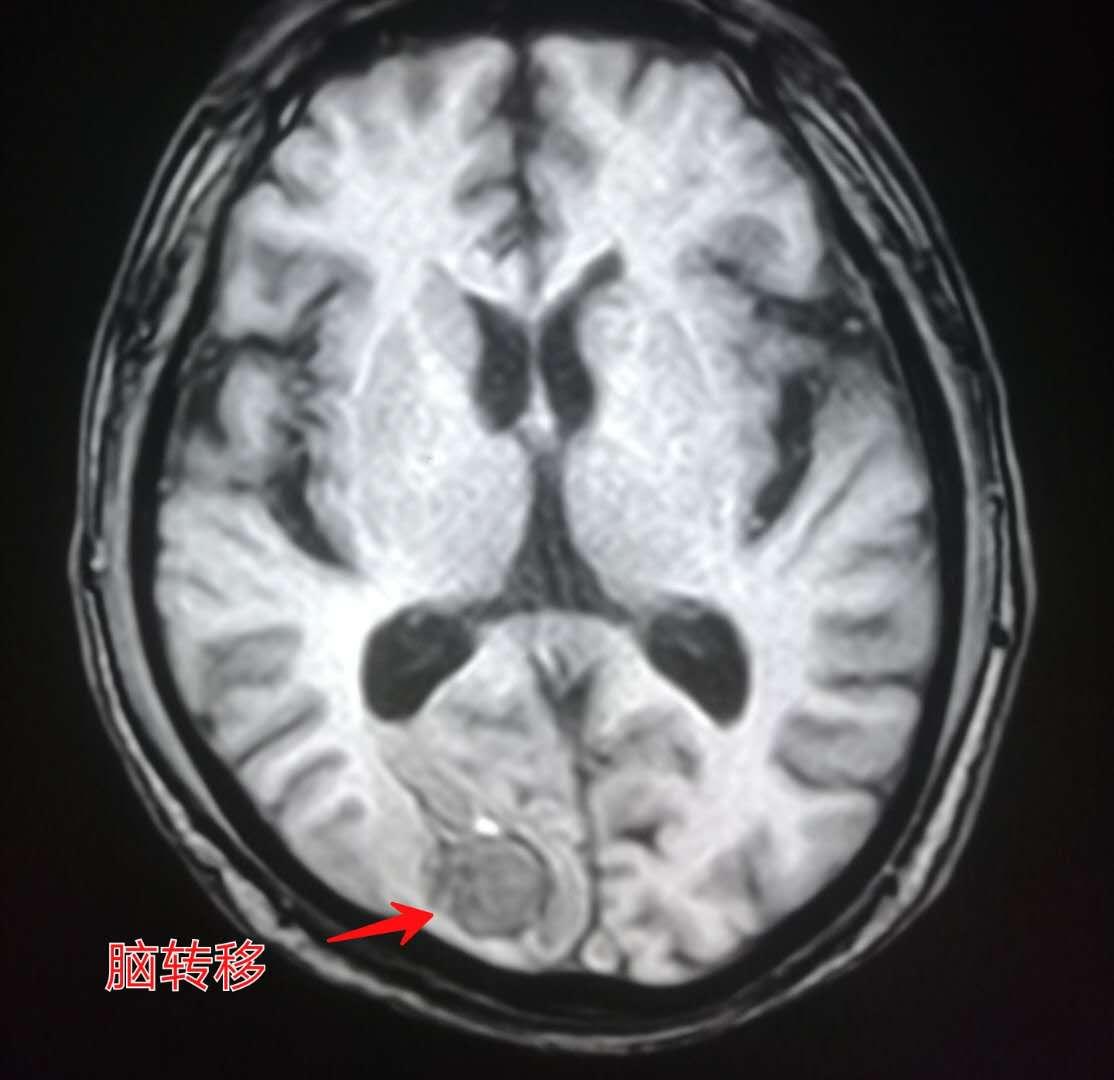

下图就是上周夜班遇到的那位老人,老爷子是一位退休干部,喜欢音乐,在家里弹钢琴的时候突然感觉左侧小指和无名指使不上力,按不动琴键了。

来医院做了脑部核磁共振,发现了脑转移瘤:

紧接着做了胸部CT,证实为右侧肺癌,老人没有任何肺部症状:

上图这位老人就是因为视物模糊,脑部核磁共振(MR)发现脑转移瘤。